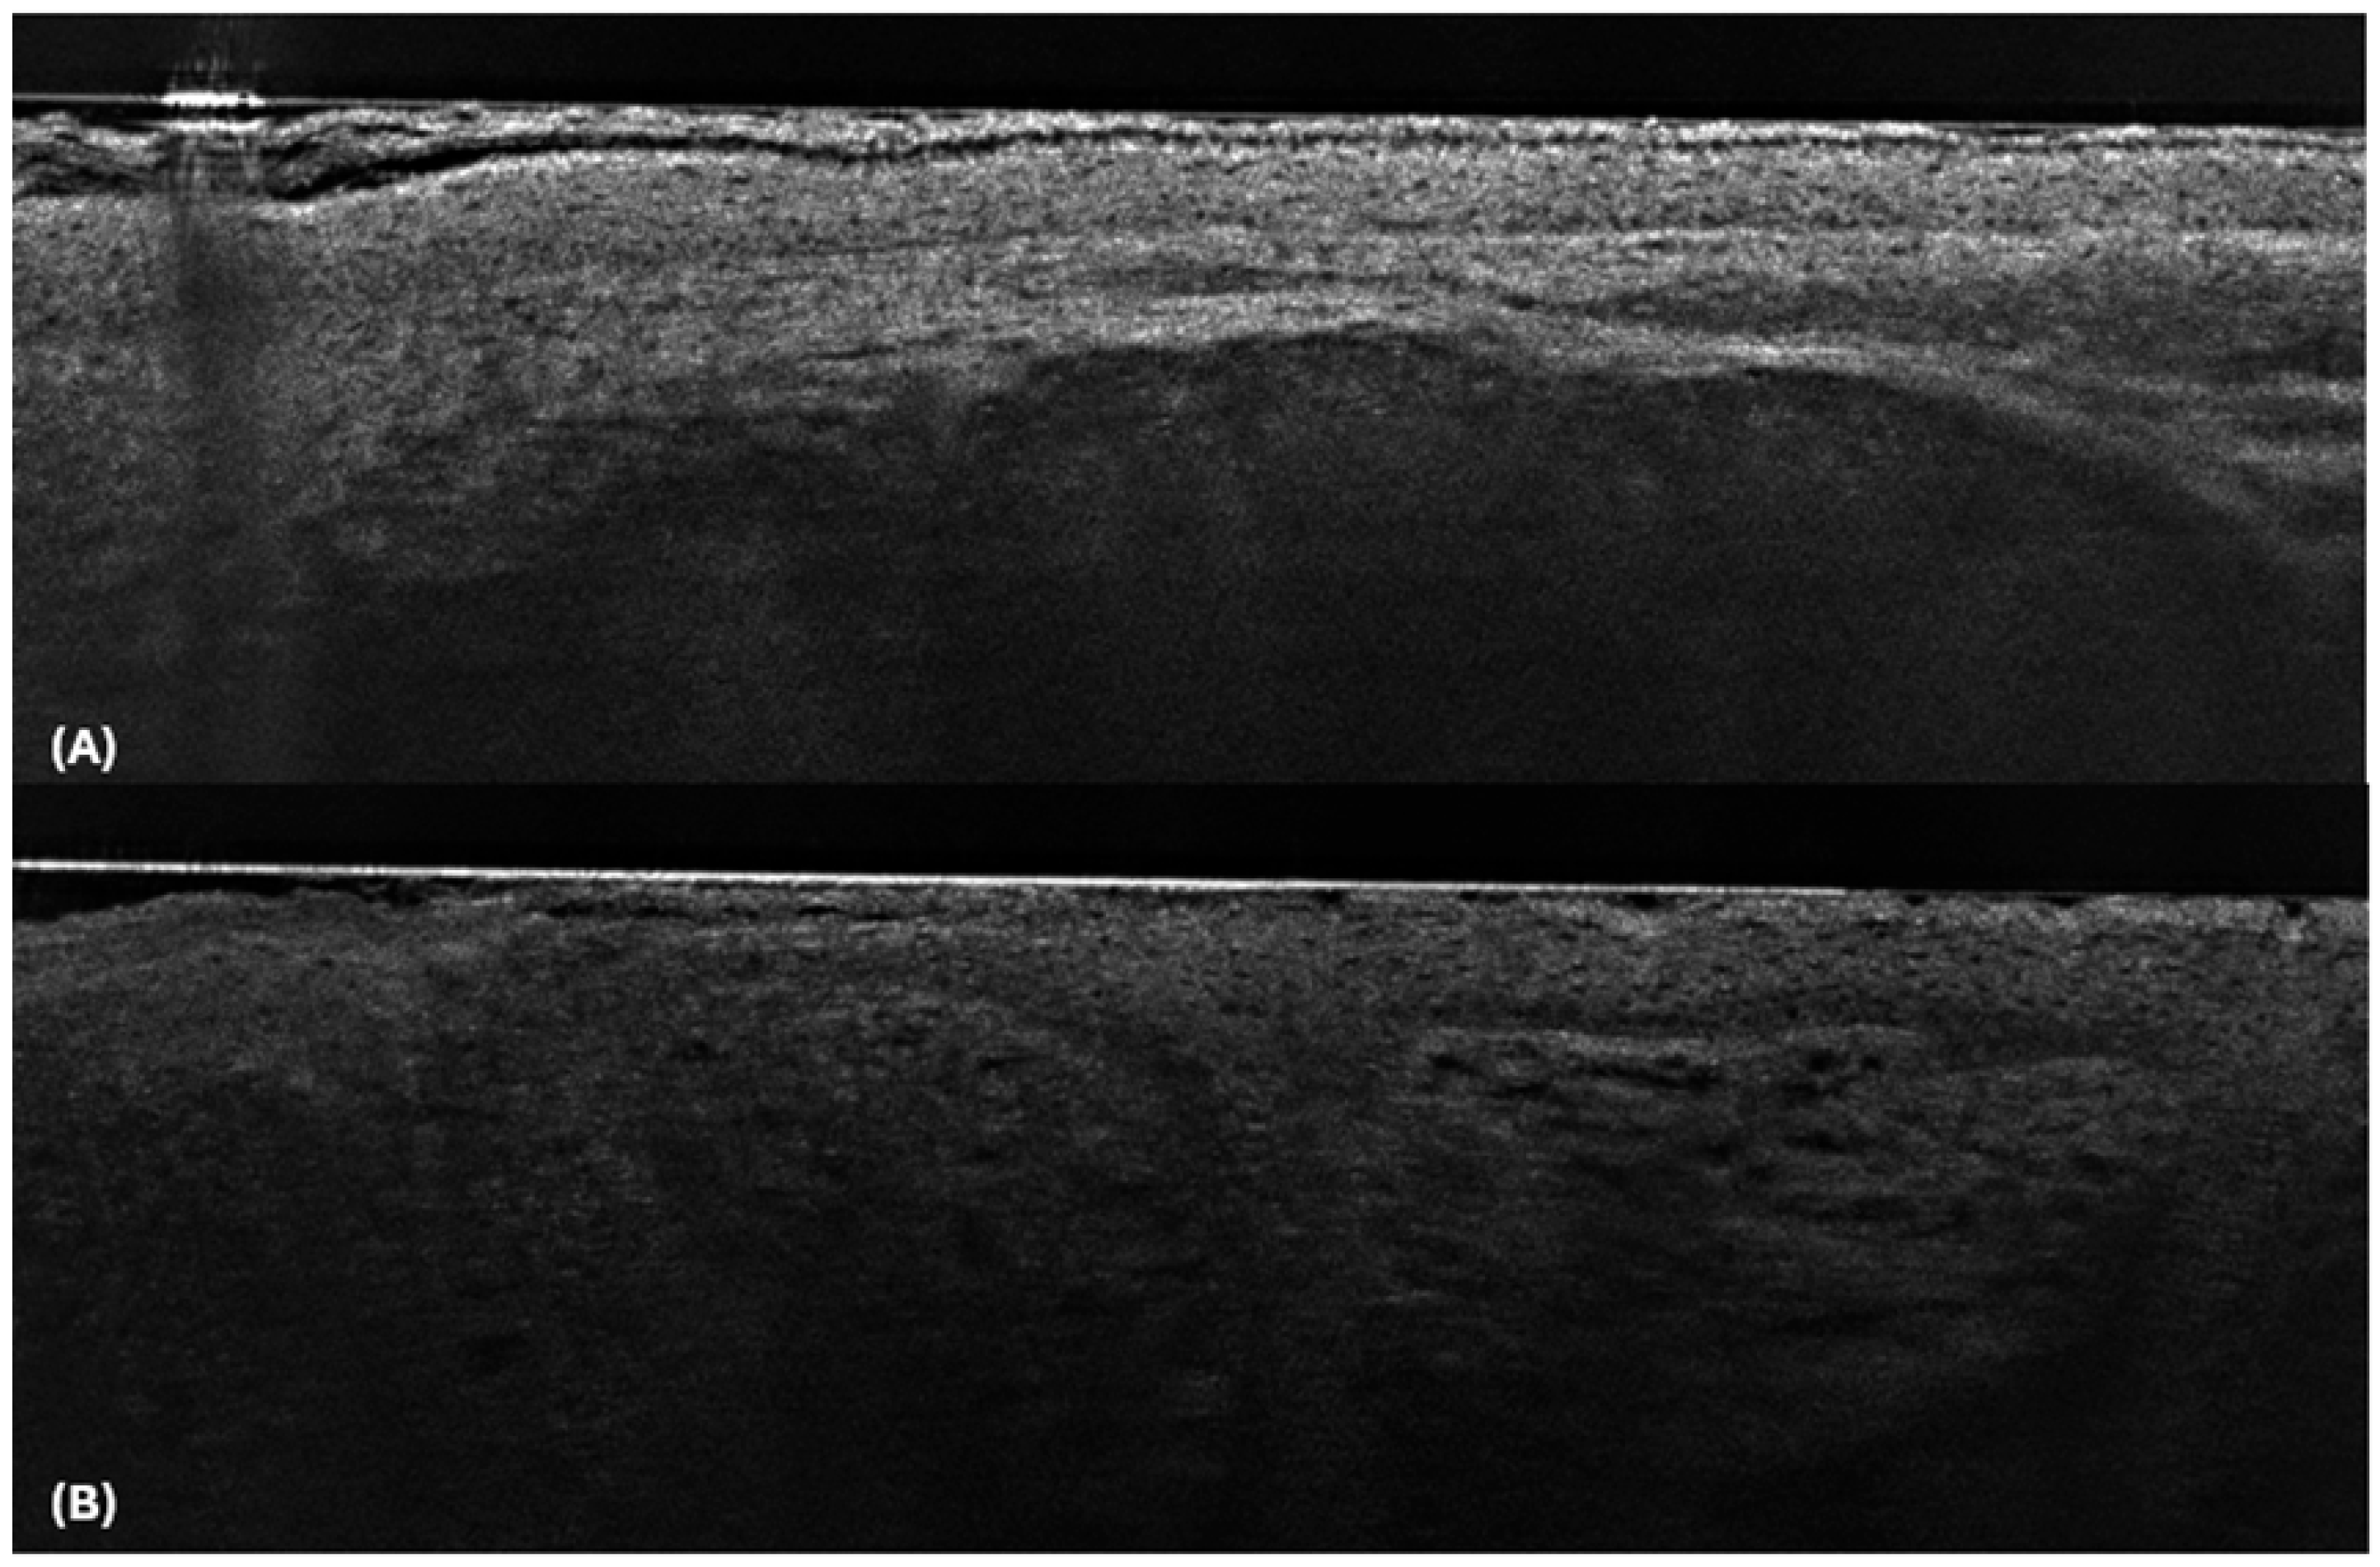

| Skin lesions other than BCC | |

| Actinic keratosis |

|

| SCC in situ/Bowen disease |

| SCC |

| Dermal Naevus |

| Seborrhoeic keratosis |

| Inflammatory Skin conditions |

| Sebaceous hyperplasia |